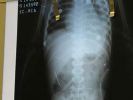

2 yaşındaki çocuğun vücudunda 50 dikiş iğnesi bulundu

Brezilya'nın başkenti Brasilia'da, 2 yaşındaki bir erkek çocuğunun vücuduna 50 dikiş iğnesi saplandı.

Brezilyalı doktorlar, iğnelerin ameliyatla çıkarılacağını, ancak bazı iğnelerin, karaciğere yakın olması nedeniyle çıkarılmasının tehlikeli olacağını ve bu iğnelerin çocuğun vücudunda bırakılacağını kaydetti.

Bazı iğnelerin çocuğun akciğerine de girdiği ve doktorların ameliyat için çocuğun nefes almasının düzelmesini bekledikleri belirtildi.